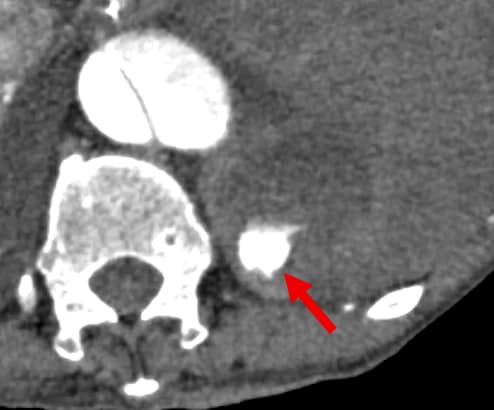

背景として、5年前に急性大動脈解離に対し全弓部置換術を施行されており、1か月前に人工血管感染のため開胸ドレナージおよび緊急予防的TEVARが施行されている。その1週間後、待機的に再全弓部置換術および大網充填が施行された。手術は問題なく終了したものの、術後9日に創部皮下の血腫を認めた。術後12日には胃管からの黒色排液や貧血の進行が認められ、上部消化管内視鏡検査が施行されたが活動性出血は指摘できず、出血源精査のため造影CT検査が施行された。左第11肋間動脈より活動性出血の所見があり、緊急的TAEを施行した。その後貧血の進行なく経過している。

今回の症例は、術後にある程度の日数が経過してから貧血の進行が顕在化していた。術直後から左胸水の増加が緩徐であったことや胃管から黒色排液を認めたことから、まず上部内視鏡検査が施行され、胸腔内の出血は積極的に疑われていなかった。実際、後方視的にも今回のCT以外では血胸を認めず、高頻度に撮影されていた胸部単純写真(臥位)では有意な変化は認められていなかった。そこで今回の撮像では胸部~骨盤部にかけて広範囲の活動性出血の検索が目的となっている。早期動脈相により動脈性の出血が同定でき、後期相の撮像により仮性動脈瘤等との鑑別も可能になっている。また、非造影検査により血性胸水の同定や石灰化と濃染域との鑑別も容易になっている。薄層やMPRの画像も作成されており責任血管の同定がしやすくなるとともに、治療(TAE)の一助にもなっている。